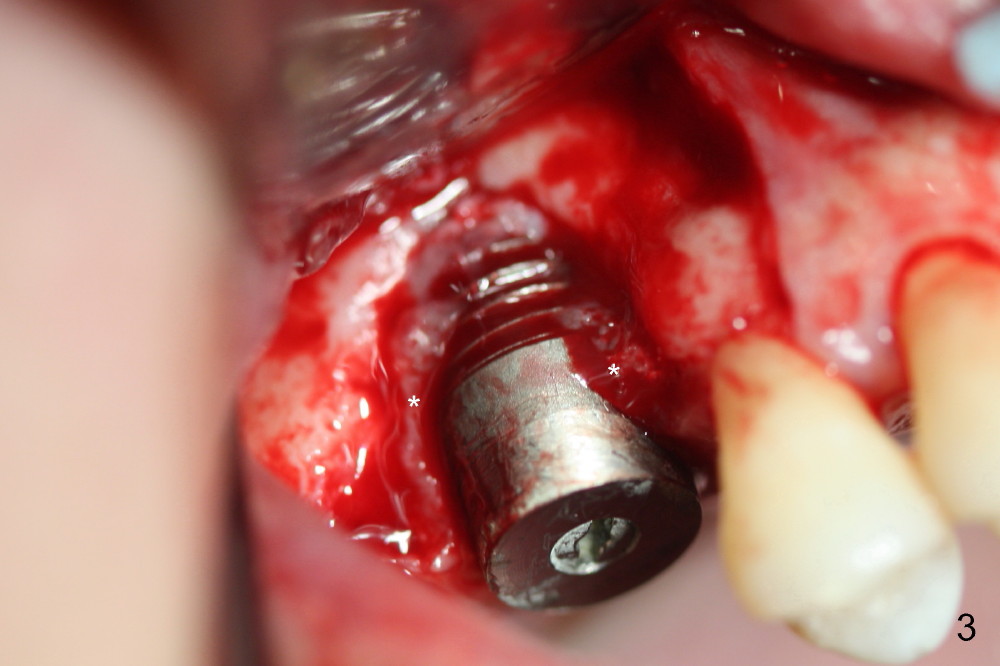

The surgery is finished as planned. Fig.2,3 (intraop photos) show thread exposure. The fistula is closed with perio glue. The defect appears to be a preexisting condition. Bone graft may be not enough or get infected. Or the implant is oversized, or placed too buccally (because of palatal defect).